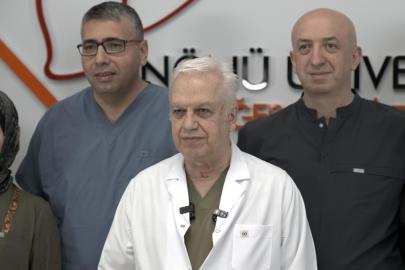

İnönü Üniversitesi Turgut Özal Tıp Merkezi'nde Kardiyoloji Uzmanı Prof. Dr. Hasan Pekdemir tarafından gerçekleştirilen renal arter denervasyonu işlemiyle, ilaç tedavisine yanıt vermeyen genç hastanın tansiyonu kontrol altına alındı. Bölge için ilk olan uygulama, dirençli hipertansiyon hastalarına umut oldu.

İnönü Üniversitesi Turgut Özal Tıp Merkezi Kardiyoloji Anabilim Dalı Öğretim Üyesi Prof. Dr. Hasan Pekdemir ve ekibi tarafından gerçekleştirilen başarılı renal arter denervasyonu işlemiyle hasta sağlığına kavuştu.

Bölgede bir ilk ve Malatya'da ilk kez gerçekleştirilen işlem hakkında İLKHA muhabirine konuşan Prof. Dr. Hasan Pekdemir, uygulamanın gebelik planı bulunan ancak tedavisinin bunu sınırlandırdığı genç bir hastaya başarıyla yapıldığını ve tansiyon değerlerinin kontrol altına alındığını ifade etti.

Prof. Dr. Hasan Pekdemir

Pekdemir "Gebelik durumunda birçok tansiyon ilacı kullanılamıyor. Bu nedenle hastamız için en uygun seçenek renal arter denervasyonu oldu. İşlemi başarıyla gerçekleştirdik ve tansiyon değerlerini kontrol altına aldık. Eğer hastamız gebe kalırsa, gebeliğe engel olmayan çok sınırlı ilaçlarla bile tansiyon kontrolü sağlanabilecek bir düzeye ulaşmış olacağız." dedi.

Hipertansiyonun dünya genelinde en yaygın sağlık sorunlarından biri olduğuna dikkat çeken Prof. Dr. Pekdemir, özellikle belirli bir yaşın üzerindeki bireylerde görülme oranının yüzde 50'ye kadar ulaştığını ifade etti. Türkiye'de ise hipertansiyonun tedavi ve takibinde ciddi eksiklikler bulunduğunu belirten Pekdemir, hastalığın çoğu zaman belirti vermeden ilerlediğini ve bu nedenle "sinsi" olarak nitelendirildiğini söyledi.

Pekdemir, Yüksek tansiyon kontrol altına alınmadığında kalp hastalıkları, inme yani felç, böbrek yetmezliği ve diyalize kadar giden ciddi tablolar ortaya çıkabiliyor. Aynı zamanda diğer hastalıkların riskini de artıran temel bir sağlık sorunu." dedi.

Hipertansiyon tedavisinde bazı hastalarda ilaçlara rağmen yeterli yanıt alınamadığını belirten Pekdemir, bu durumun "dirençli hipertansiyon" olarak tanımlandığını ifade etti. Pekdemir "Bir hastanın üç ya da dört farklı tansiyon ilacı kullanmasına, bunlardan birinin idrar söktürücü olmasına rağmen tansiyon kontrol altına alınamıyorsa burada dirençli hipertansiyondan söz ediyoruz. Bu hastalarda çoğu zaman beşli tedavilere kadar çıkıyoruz, dozları artırıyoruz ancak yine de istenilen kan basıncı seviyesine ulaşamayabiliyoruz." diye konuştu.

Dirençli hipertansiyonun altında yatan önemli mekanizmalardan birinin sempatik sinir sistemi olduğunu dile getiren Pekdemir, "Sempatik sinir sistemi kalp hızını artıran ve tansiyonu yükselten bir sistem. Bu sistemin sürekli aktif olması durumunda beyne giden uyarılar artıyor ve böbrek damarlarında daralma meydana geliyor. Bu da böbrekte tuz ve su tutulmasına neden olarak tansiyonun sürekli yüksek seyretmesine yol açıyor." ifadelerini kullandı.

Bu noktada devreye giren renal arter denervasyonu yönteminin, böbrek damarlarının etrafındaki sempatik sinirlerin ablasyon yöntemiyle etkisiz hale getirilmesine dayandığını belirten Pekdemir, yöntemin etkisini şu sözlerle anlattı:

"Bu sinirleri yaktığımızda tansiyonu yükselten sinyallerin beyne iletilmesi engelleniyor. Böbreğe giden yanlış uyarılar ortadan kalkıyor. Bunun sonucunda damarlar genişliyor, tuz ve su tutulumu azalıyor ve hastanın tansiyonunda ciddi düşüşler sağlanıyor."

Yöntemin her hasta için uygun olmadığını, dikkatli hasta seçimi gerektiğini vurgulayan Pekdemir, özellikle genç, ilaç kullanamayan veya sempatik aktivitesi yüksek hastalarda çok yüksek başarı oranları elde edildiğini söyledi. Pekdemir "Bu hasta grubunda yüzde yüze yakın fayda görebiliyoruz. Bazı hastalar tamamen ilaçsız kalabiliyor, bazı hastalarda ise beşli tedaviler bir ya da iki ilaca kadar düşebiliyor." dedi.

Söz konusu işlemin Malatya'da ilk kez gerçekleştirildiğini belirten Pekdemir, uygulamanın genç bir hastaya yapıldığını ifade etti. Hastanın beş farklı ilaç kullanmasına rağmen tansiyonunun kontrol altına alınamadığını ve sık sık ataklar yaşadığını belirten Pekdemir, ayrıca hastanın gebelik planı bulunmasının tedavi seçeneklerini sınırladığını söyledi.

Pekdemir, "Gebelik durumunda birçok tansiyon ilacı kullanılamıyor. Bu nedenle hastamız için en uygun seçenek renal arter denervasyonu oldu. İşlemi başarıyla gerçekleştirdik ve tansiyon değerlerini kontrol altına aldık." dedi.

"Etkisi 24 saatte başlıyor, kalıcı sonuç 3 ayda"

İşlemin etkisinin kısa sürede başladığını ancak kalıcı sonuçların zamanla ortaya çıktığını ifade eden Pekdemir, "Renal denervasyon sonrası etkiler yaklaşık 24 saat içinde görülmeye başlıyor. Ancak dokunun iyileşmesi ve sürecin tamamen oturması yaklaşık 3 ayı buluyor. Bu sürede hastayı yakından takip ediyoruz. Üç ayın sonunda çok daha belirgin ve kalıcı tansiyon düşüşleri gözlemliyoruz." diye konuştu.

Hastanın ilerleyen süreçte ya tamamen ilaçsız kalabileceğini ya da çok daha düşük dozlarla tansiyonunu kontrol edebileceğini belirten Pekdemir "Eğer hastamız gebe kalırsa, gebeliğe engel olmayan çok sınırlı ilaçlarla bile tansiyon kontrolü sağlanabilecek bir düzeye ulaşmış olacağız." dedi.

İnönü Üniversitesi Turgut Özal Tıp Merkezi'nin ileri düzey kardiyolojik tedavilerin yoğun şekilde uygulandığı bir merkez olduğunu vurgulayan Pekdemir, özellikle çoklu ilaç kullanmasına rağmen sonuç alamayan veya ilaç kullanması sakıncalı olan hastaların bu yöntem açısından değerlendirilmesi gerektiğini belirtti.

Pekdemir, uygun hastaların merkeze başvurarak bu tedaviden fayda görebileceğini sözlerine ekledi.